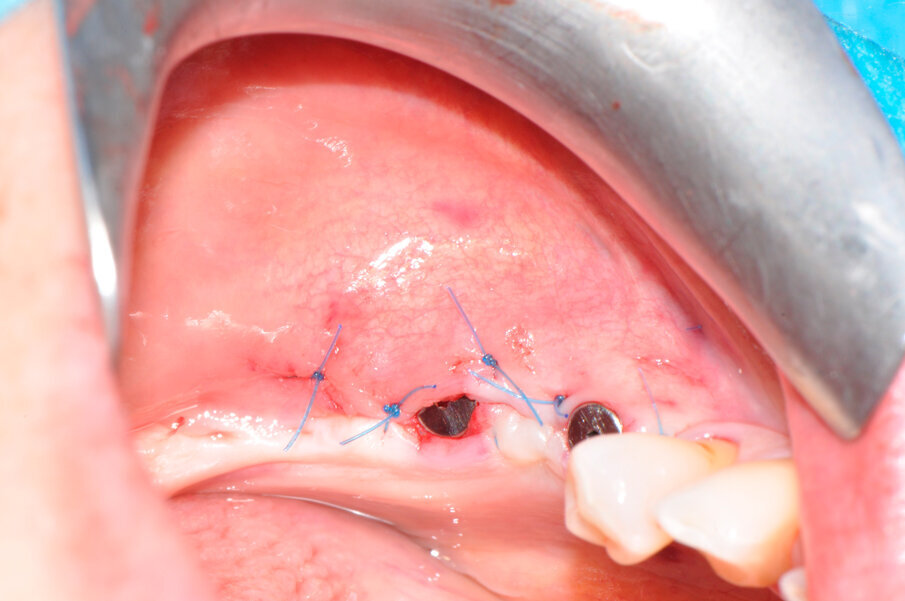

La paziente forniva il proprio consenso informato. La paziente è stata sottoposta 5 giorni prima dell’intervento a una igiene orale professionale al fine di risolvere la condizione infiammatoria relativa alla mucosa e predisporre la zona perimplantare all’intervento per la rigenerazione ossea, ottenendo uno stato ottimale dei tessuti molli, compatibilmente con la patologia in atto (Fig. 2). Si è prescritta una terapia antibiotica con amoxicillina/acido clavulanico (Augmentin, Glaxo-SmithKline, Verona, Italy) tre giorni prima della chirurgia ogni 12 ore e per i successivi 8-10 giorni. In seguito alla seduta di igiene pre-intervento, la paziente è stata anestetizzata localmente con articaina 1:100.000 per procedere alla fase chirurgica.

L’innesto è stato protetto con due membrane, opportunamente sagomate e forate per adattarsi attorno a ciascun impianto (Fig. 7). L’operazione è terminata con la sutura dei lembi gengivali tramite filo in poliammide non riassorbibile (Monomyd 4-0, Butterfly, Cavenago) e il posizionamento di due viti di guarigione (Fig. 8). La sutura è stata rimossa a 12 giorni dall’atto chirurgico. Una radiografia di controllo al termine dell’intervento ha confermato l’effettivo ripristino dei volumi ossei perimplantari (Fig. 9). Durante il periodo di guarigione e ai successivi controlli, non si sono osservati segni di sofferenza gengivale (Fig. 10). La paziente non ha lamentato alcuna sintomatologia spontanea o evocata. Al controllo a 3 mesi, l’esame radiografico mostrava il mantenimento dei profili ossei perimplantari (Fig. 11). Sono state quindi rimosse le viti di guarigione e riposizionate le corone.

Fig. 2 – Aspetto clinico delle mucose perimplantari al momento dell’atto chirurgico.

Fig. 8 - La sutura al termine dell’intervento.